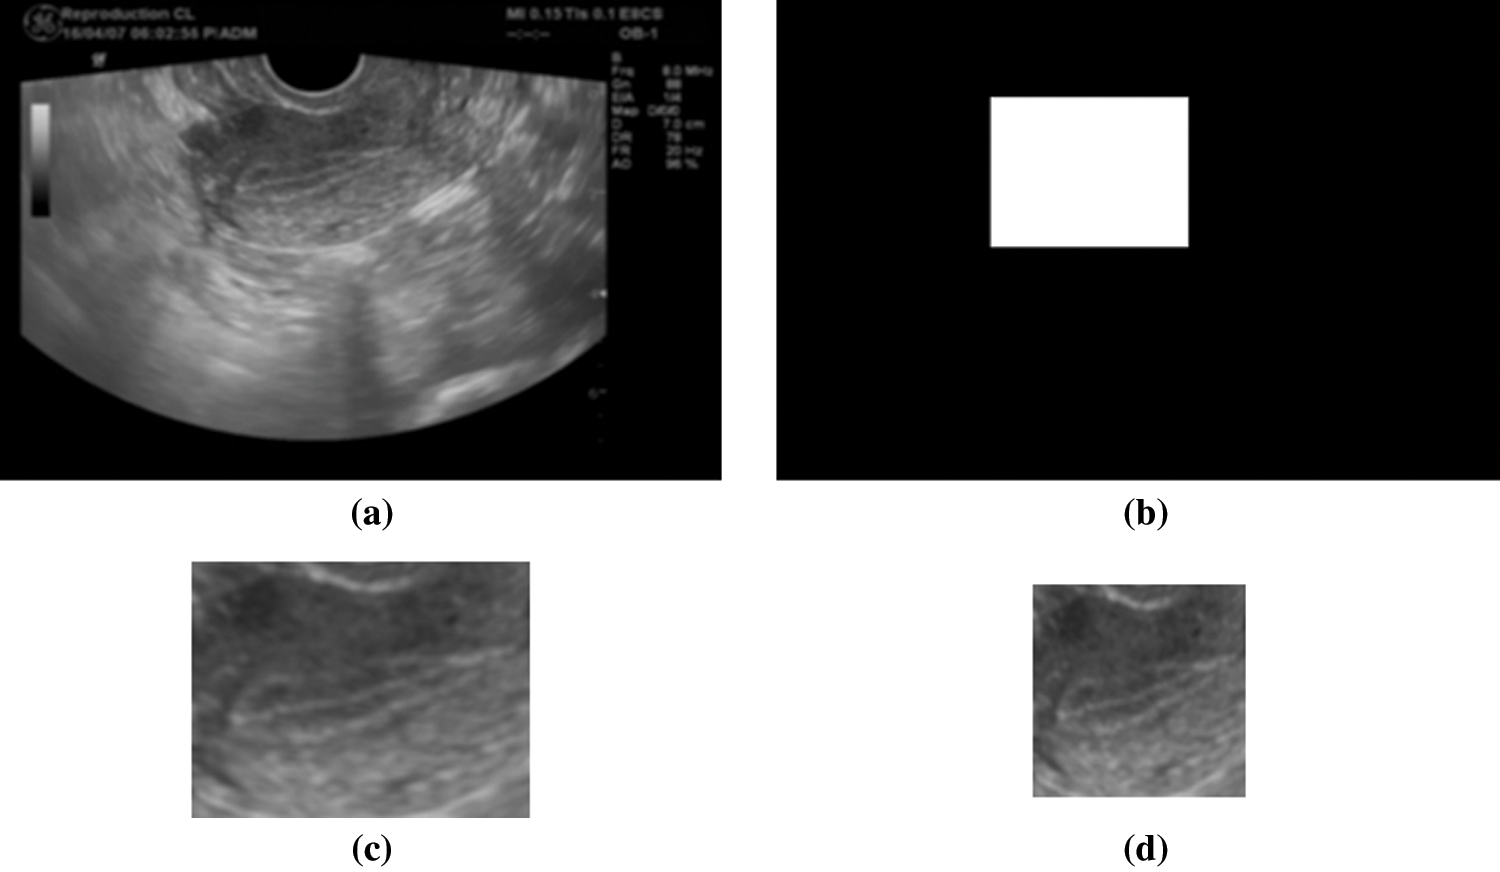

An averaging filter of 5 × 5 pixels is applied to the ultrasonic images as preprocessing. An average image is generated every second from the movie file by calculating an average for a time axis. 30 images are generated from 30 second movie by this process. An endometrial region is extracted from the average image by using a mask image. The mask image has been manually generated in advance. Fig. 2 shows original image, mask image, extracted image by the mask, and resized image. This mask works to extract endometrium region from ultrasonic images. Since an endometrial shape and direction have individual differences, the extracted region size is different from each other. Rotation processes every 60 degrees are applied to the extracted images. The obtained image is saved in 224 × 224 pixels. Fig. 2d shows the saved image of 224 × 224 pixel size. Fig. 3 shows example of the saved images. A vertical axis in Fig. 3 shows time of movie file, and horizontal axis shows rotated images. Tab. 4 shows the number of the saved images.

Figure 2: Examples of images in the mask process (a) original image (b) mask image (c) extracted image (d) resized image